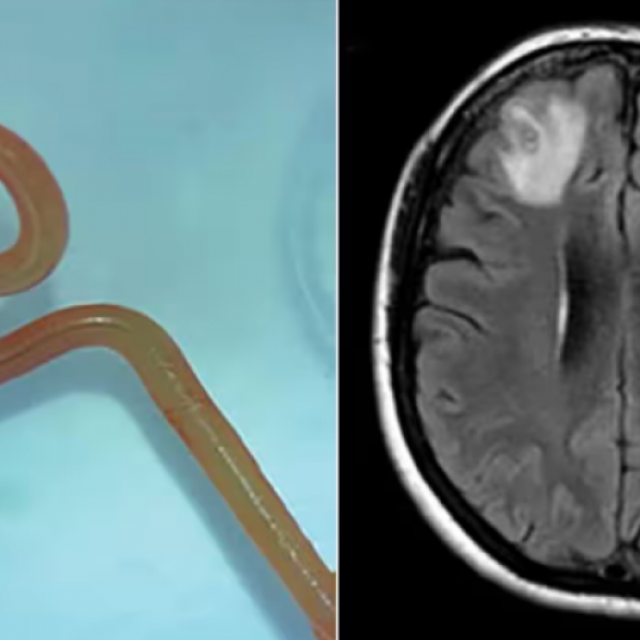

NEVJEROJATAN SLUČAJ Žena dvije godine trpjela strašne bolove, a onda je magnetska rezonanca otkrila horor: ‘Liječnici ovo nikad nisu vidjeli‘ 29.08.2023. u 10:05